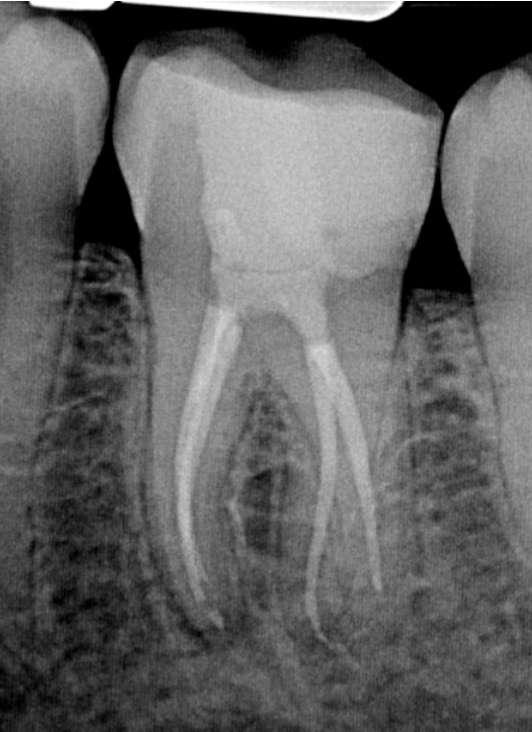

Zur koronalen Erweiterung der Kanäle wurde eine EdgeFile X7 der Größe 17.06 eingesetzt. Die Erstellung des Gleitpfads konnte rein mechanisch durchgeführt werden. Hierzu wurden EdgeFile X7 der Größe 17.04, 17.06 in alternierender Weise bis zum Erreichen der näherungsweise röntgenologisch bestimmten vorläufigen Arbeitslänge eingesetzt. Nach elektrometrischer Bestimmung der Arbeitslänge mit C-Pilot Feilen der Größe 8 und 10 erfolgte die weitere Präparation mit EdgeFile X7 der Größe 20.06, 25.06 und 30.06. Die Kanäle wurden nach der finalen Aufbereitung für 60 Sekunden mit 17% EDTA gespült. Die Abschlussspülung erfolgte schallaktiviert mit 6% NaOCl. Eine Masterpointaufnahme diente zur Verifizierung der Aufbereitung und der Passung der angepassten Guttaperchaspitzen (Abbildung 7). Nach Trocknung mit Mikroabsaugung und Papierspitzen wurden alle Kanäle in warm vertikaler Fülltechnik mit biokeramischem Sealer obturiert (Abbildung 8). Der adhäsive Verschluss erfolgte mit Bulk Fill Flow Komposit (Abbildung 9).

Abbildung 7: Masterpointaufnahme

Abbildung 8: Kontrollaufnahme nach Wurzelfüllung